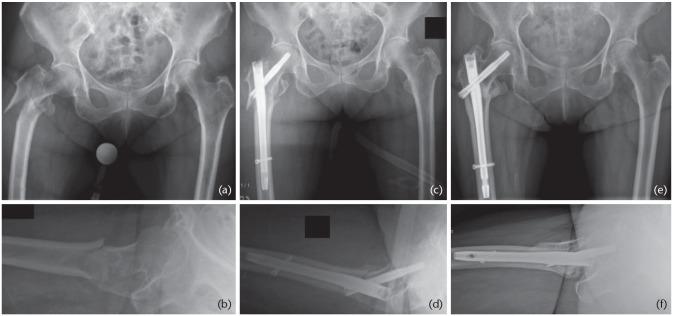

股骨转子间骨折常采用四孔侧板滑动髋螺钉装置固定,但近几十年来,人们尝试使用两孔侧板以尽量减少手术时间、手术切口、失血和术后疼痛。本综述的目的是确定两孔滑动髋螺钉结构是否是治疗AO-OTA 31-A1和A2型股骨转子间骨折的可接受选择。使用PubMed®对电子MEDLINE®数据库进行检索,如果文章报道了使用两孔滑动髋螺钉装置进行转子间骨折固定的历史、生物力学、临床或结果数据,则纳入本综述。对于AO-OTA 31-A1型单纯转子间骨折的固定,推荐采用两孔动力髋螺钉结合微创肌肉劈开入路;这种植入物在生物力学上是安全的,并允许采用微创肌肉劈开入路,这可能会带来更好的临床效果,如减少手术创伤、缩短手术时间、减少失血、减少镇痛药物使用和缩短切口长度。由于大多数综述文献都与动力髋螺钉有关,因此尚不清楚上述建议是否可扩展到任何其他滑动髋螺钉装置。对于所有其他囊外近端股骨骨折,推荐使用髓内装置。引用本文:2020;5:118-125。DOI:10.1302/2058-5241.5.190020。

https://cdn.ncbi.nlm.nih.gov/pmc/blobs/770a/7047904/d8a8d2a99165/eor-5-118-g003.jpg

https://cdn.ncbi.nlm.nih.gov/pmc/blobs/770a/7047904/5e8fe7692d64/eor-5-118-g001.jpg

https://cdn.ncbi.nlm.nih.gov/pmc/blobs/770a/7047904/7137cea077d5/eor-5-118-g002.jpg